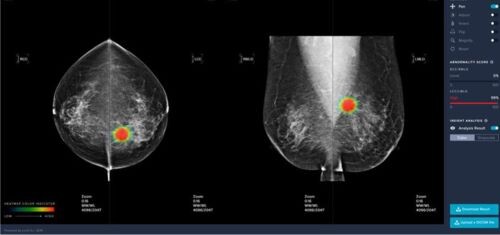

| ▲루닛의 유방암영상검출·진단보조소프트웨어 (사진= 식품의약품안전처 제공) |

이 제품은 유방암 영상검출ㆍ진단보조 소프트웨어로는 국내 처음으로 허가(제허19-493호)받았으며 악성 병변 의심 부위와 의심 정도를 색상과 확률값으로 표시해 의료진의 진단을 보조하는 소프트웨어다.

약 18만 건의 유방촬영 영상을 학습데이터로 사용한 이 제품은 악성 병변의 검출 정확도를 높이고 위양성 병변의 검출 빈도를 줄였고, 동양 여성에게 많으나 영상판독이 어려운 치밀형 유방의 판독 오류를 최소화했으며, 15초 내외의영상 분석 시간으로 의료진의 진단을 신속하게 보조할 수 있는 장점이 있다.